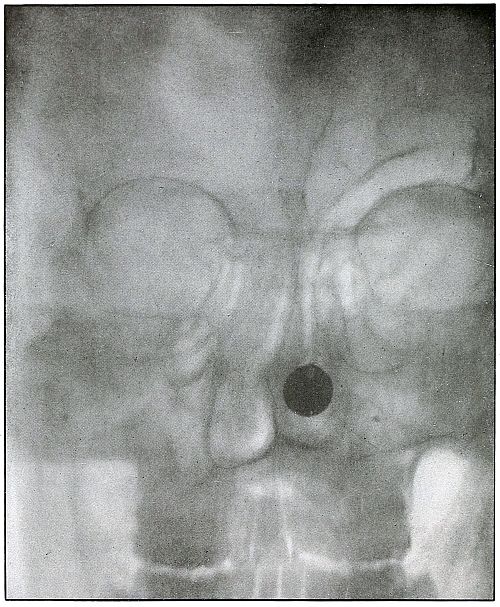

Plate 4.

[Pg 19]

Rifle—Plate 4.

HEAD.

Gunshot Fracture of the Ramus of the Lower Jaw.

Wound of entrance, over the anterior border of the right ramus.

Wound of exit, beneath the lobe of the ear.

The wound was made by a rifle bullet with the velocity of long range,

because wounds of a shrapnel ball never show such slight injury

without lodgment or without marks of lead.

The damage of the bone was very slight, as only a superficial fragment

was chipped off. There were no signs of primary infection. Reaction

and periostitis suggested the radiograph after infection had rarefied

the fragment, shown but very faintly on the left side of the plate.

The postero-anterior skull radiograph was made with the face

superimposed upon the photographic plate.

Treatment, incision and drainage.

Results, good.